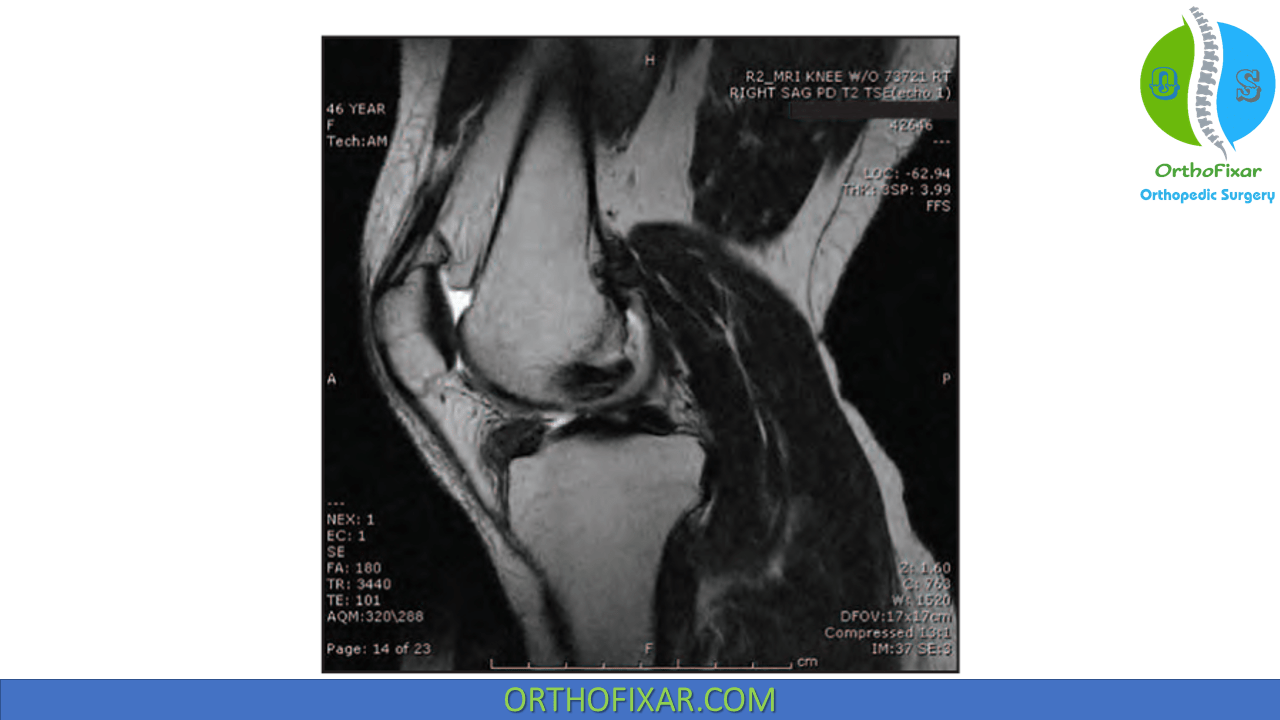

From www.researchgate.net

MRI knee of 12yearold boy, three months after arthroscopic Arthroscopic Knee Surgery Synovectomy It may be performed either. A synovectomy is a surgical procedure for the treatment of synovitis in which part of the synovium of a joint is removed. Synovectomy of the knee is a procedure that has multiple indications, of which the most common are septic arthritis, inflammatory arthritis, and synovial tumors. Removal of loose bodies, synovectomy of the posteromedial compartment.. Arthroscopic Knee Surgery Synovectomy.